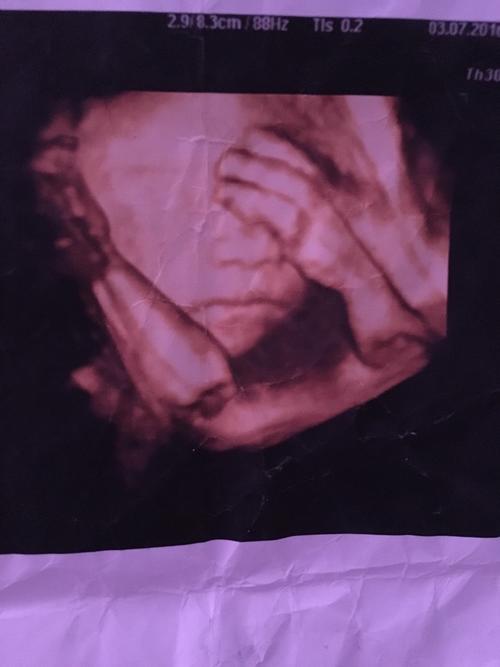

胎儿在子宫里的真实照片(组图)(2)

这是长到11个星期的胎儿.

宝妈们会看三维胎儿照片吗?我怎么没看见宝宝的眼睛呢